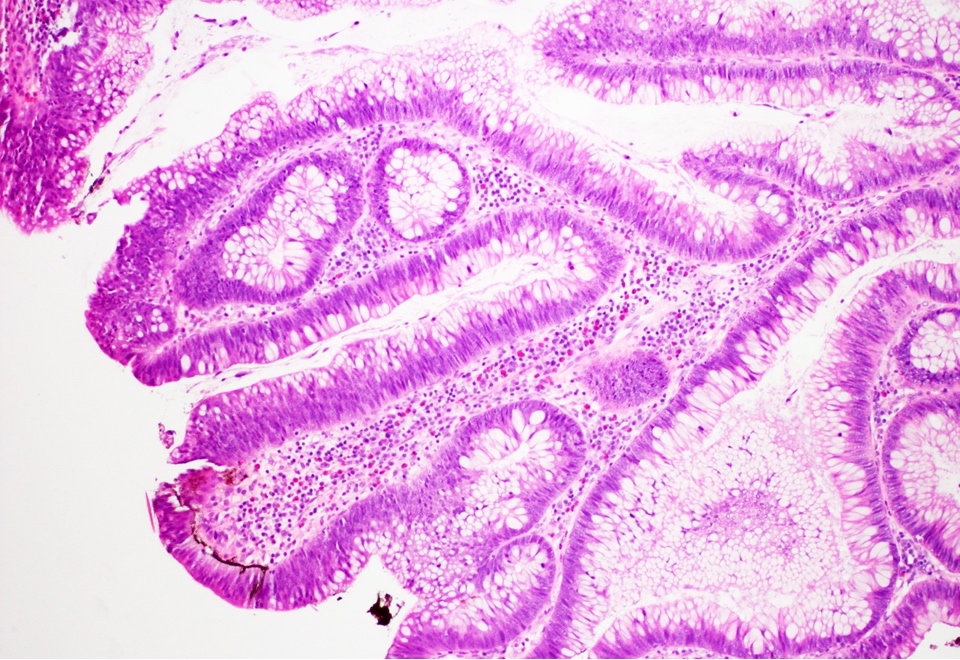

Microscopic (histologic) description

- Low grade dysplasia:

- Preserved nuclear polarity

- Pseudostratified, crowded, elongated and hyperchromatic nuclei

- Lack of surface maturation, i.e. abnormalities persist to surface

Microscopic (histologic) images